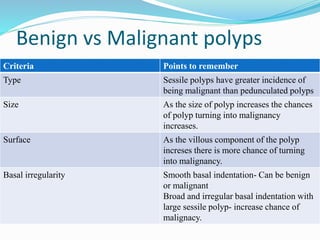

This document discusses colorectal polyps. It defines polyps and describes their types, including neoplastic and non-neoplastic polyps. It discusses adenomatous polyps in depth, noting their malignant potential increases with size over 1cm and villous architecture. Radiological diagnostic methods for polyps including single and double contrast barium enema and CT colonography are explained. The document provides an overview of polyp pathogenesis and genetic syndromes like FAP that increase cancer risk.